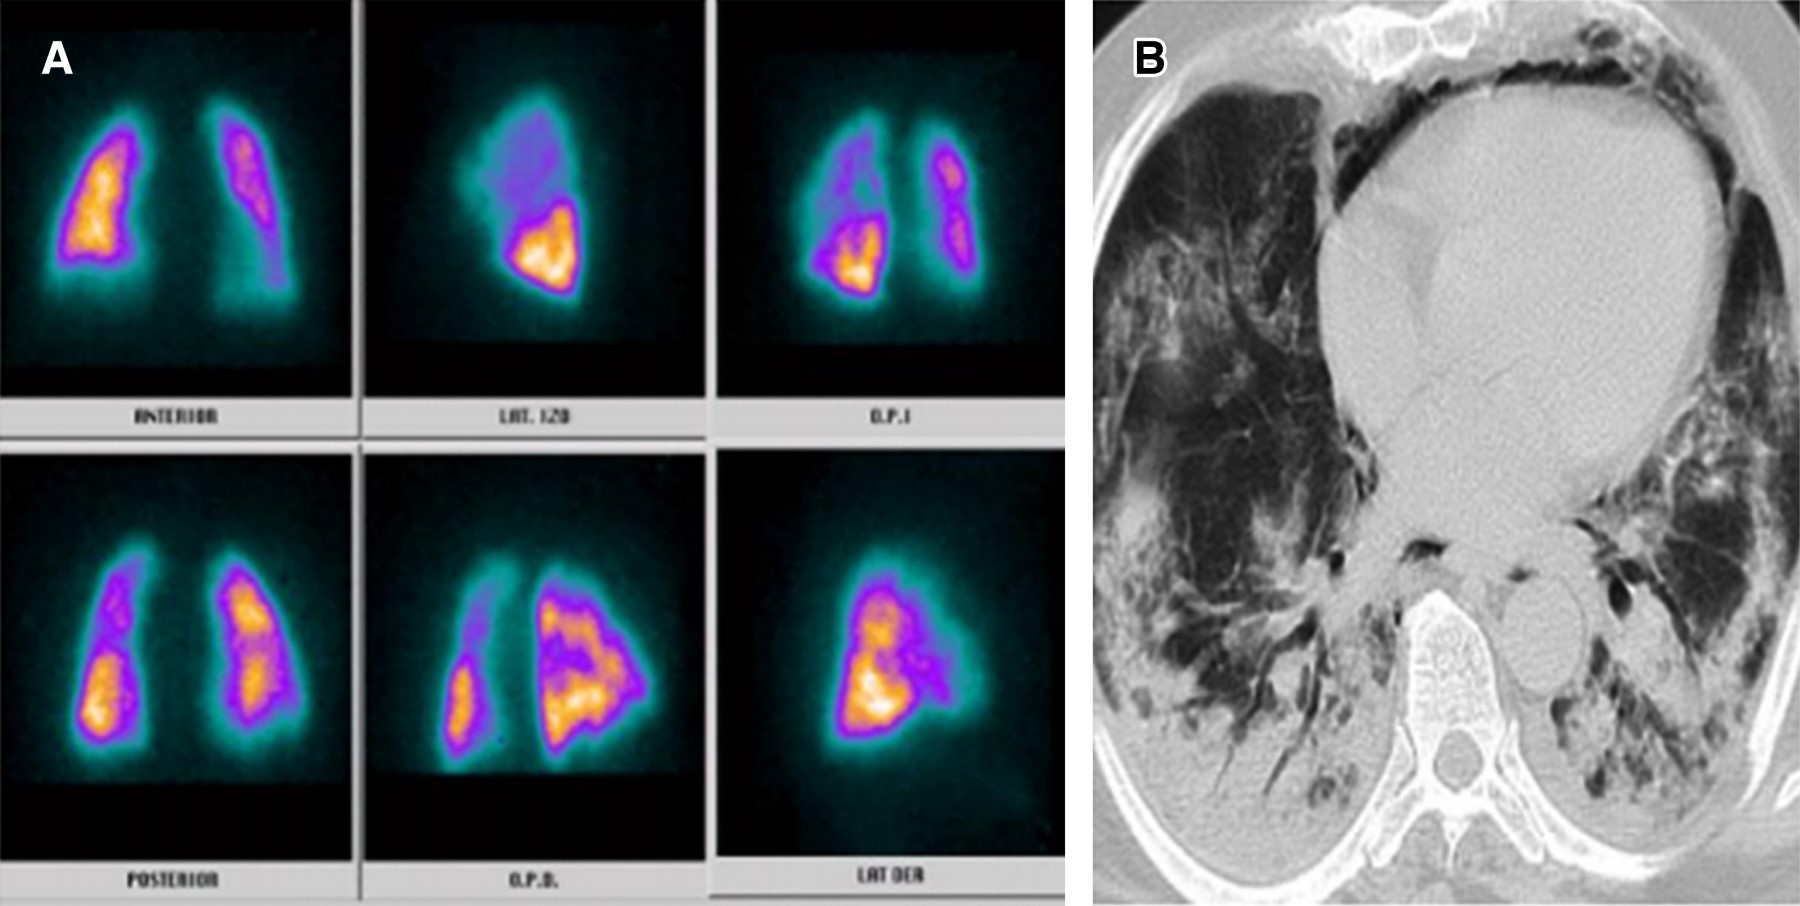

La infección por nuevo coronavirus es una entidad clínica altamente letal que trae consigo serias disfunciones celulares en primera línea de defensa, lo cual genera potentes mecanismos de hipercoagulabilidad mediados por reclutamiento de células inflamatorias.1 Uno de ellos direccionado por la disfunción del polimorfonuclear a partir del receptor 2 de enzima convertidora de angiotensina generado por la interacción de la fenilalanina ubicada en la porción 486 de la proteína de espiga del coronavirus, constituyéndose como el efecto más quimiotáctico existente, incluso superior al de la interleucina 8 (IL-8).2 A partir de esta situación, el reclutamiento del neutrófilo trae consigo la formación de una fina red inflamatoria inductora de integrinas denominadas NET (Neutrophil Extracellular Traps), produciendo activación de la vía intrínseca de la coagulación a partir del factor XII de Hageman. Adicionalmente, la muerte programada de dichas células, mediante la inducción de apoptosis, ocasiona liberación de histonas y restos de ADN, lo que precipita la formación de trombina.3,4 Por otro lado, la infección por nuevo coronavirus altera la respuesta del huésped al inóculo mediante modificación de los micro-ARN linfocitarios, lo que ocasiona disfunción del fagosoma natural en estadios de inmunocompetencia exacerbada o inmunosupresión manifiesta que a la postre desencadena estrés oxidativo, liberando grupos de proteínas de elevada movilidad (High Mobility Protein Box 1 [HMGB1]) y generando inflamación, coagulación y apoptosis.5 Pero, sin duda alguna, la linfopenia inducida por el coronavirus tipo 2 se constituye como el determinante más letal de trombosis mediante activación de la vía extrínseca e intrínseca de la coagulación, de la mano de un influjo descomunal de trombina. Se han identificado tres mecanismos de muerte celular programada en el linfocito de pacientes con la enfermedad por coronavirus del 2019 (COVID-19); uno de ellos es por activación del factor de transcripción nuclear y factor nuclear kappa beta, otra es por la activación del mitógeno p37 de la proteincinasa y la más deletérea mediante autofagocitosis determinante de un potente estado protrombótico.6 Con base en el conocimiento de los escenarios disfuncionales hematológicos durante la infección por nuevo coronavirus, se hace perentoria la predicción de enfermedad pulmonar tromboembólica, existiendo la duda razonable entre la prevención y la terapia antitrombótica, motivo por el cual la presencia de marcadores de actividad de fibrinolítica debe ser validada en tiempo presente y real. Teniendo en cuenta la mejor sensibilidad y especificidad disponible, las diferentes técnicas de enzimas líticas de inmunoensayo, hemaglutinación y látex deben someterse a consideración durante la estratificación diagnóstica.7,8 Una vez discriminados los pacientes con SARS-CoV-2 con pretest clínico medio para enfermedad pulmonar tromboembólica con reporte de dímero D por técnica de látex positivo y cuyos resultados de angio-TAC descartaron tromboembolia pulmonar (TEP); se les documentó, desde el punto de vista imagenológico, los defectos segmentarios de distribución vascular con morfología triangular de base externa y vértice interno por medicina nuclear, los cuales se correlacionaron muy de cerca con hallazgos en escanografías simples de tórax con atelectasias, efusión pleural y condensaciones, así mismo la presencia de alta probabilidad para TEP se validó por criterios de PISAPED (Figura 1, 2, 3, 4, 5, 6 y 7).9

Figura 1

Figura 2

Figura 3

Figura 4

Figura 5

Figura 6

Figura 7